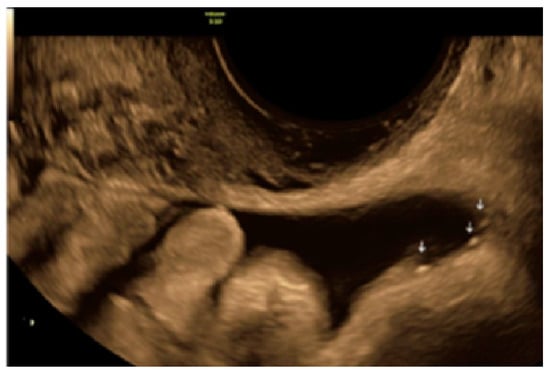

- The lesion may be convex, protruding from the peritoneal surface into the peritoneal cavity (we called this “bulging”), or it may appear as a concave defect in the peritoneum (we called this a “pocket”).